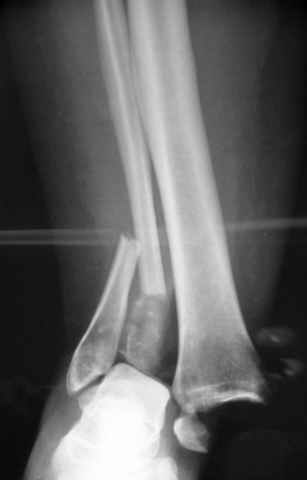

На прямой проекции послеоперационного Рг макроскопически все выглядит очень анатомично, при микроскопическом ( :-)) ) рассмотрении можно все-таки заметить вальгизацию тарана, суставная щель в латеральном отделе сустава несколько уже , чем в медиальном при отсутствии латерального смещения тарана. У меня был аналогичный случай (без LISS , без мини доступа) с вальгусным наклоном тарана при восстановленном ankle mortise при последовательном наблюдении с интервалами в 6-8 недель в послеоперационном периоде отмечалось прогрессирующее сужение суставной щели в латеральном отделе сустава, закончившееся посттравматическим ОА, к счастью боли умеренные, купируемые аналгетиками или своими эндорфинами:-))(активная пациентка, у которой нет времени на болезни....) Какова жизненная ситуация в приведенном вами случае? И последнее, что я хотел бы прояснить для себя - фиксация внутренней лодыжки: я обычно комбинирую фиксацию компрессирующим винтом со спицей - по идее ротационная стабильность должна быть лучше, чем один винт, каковы ваши наблюдения в этом плане?